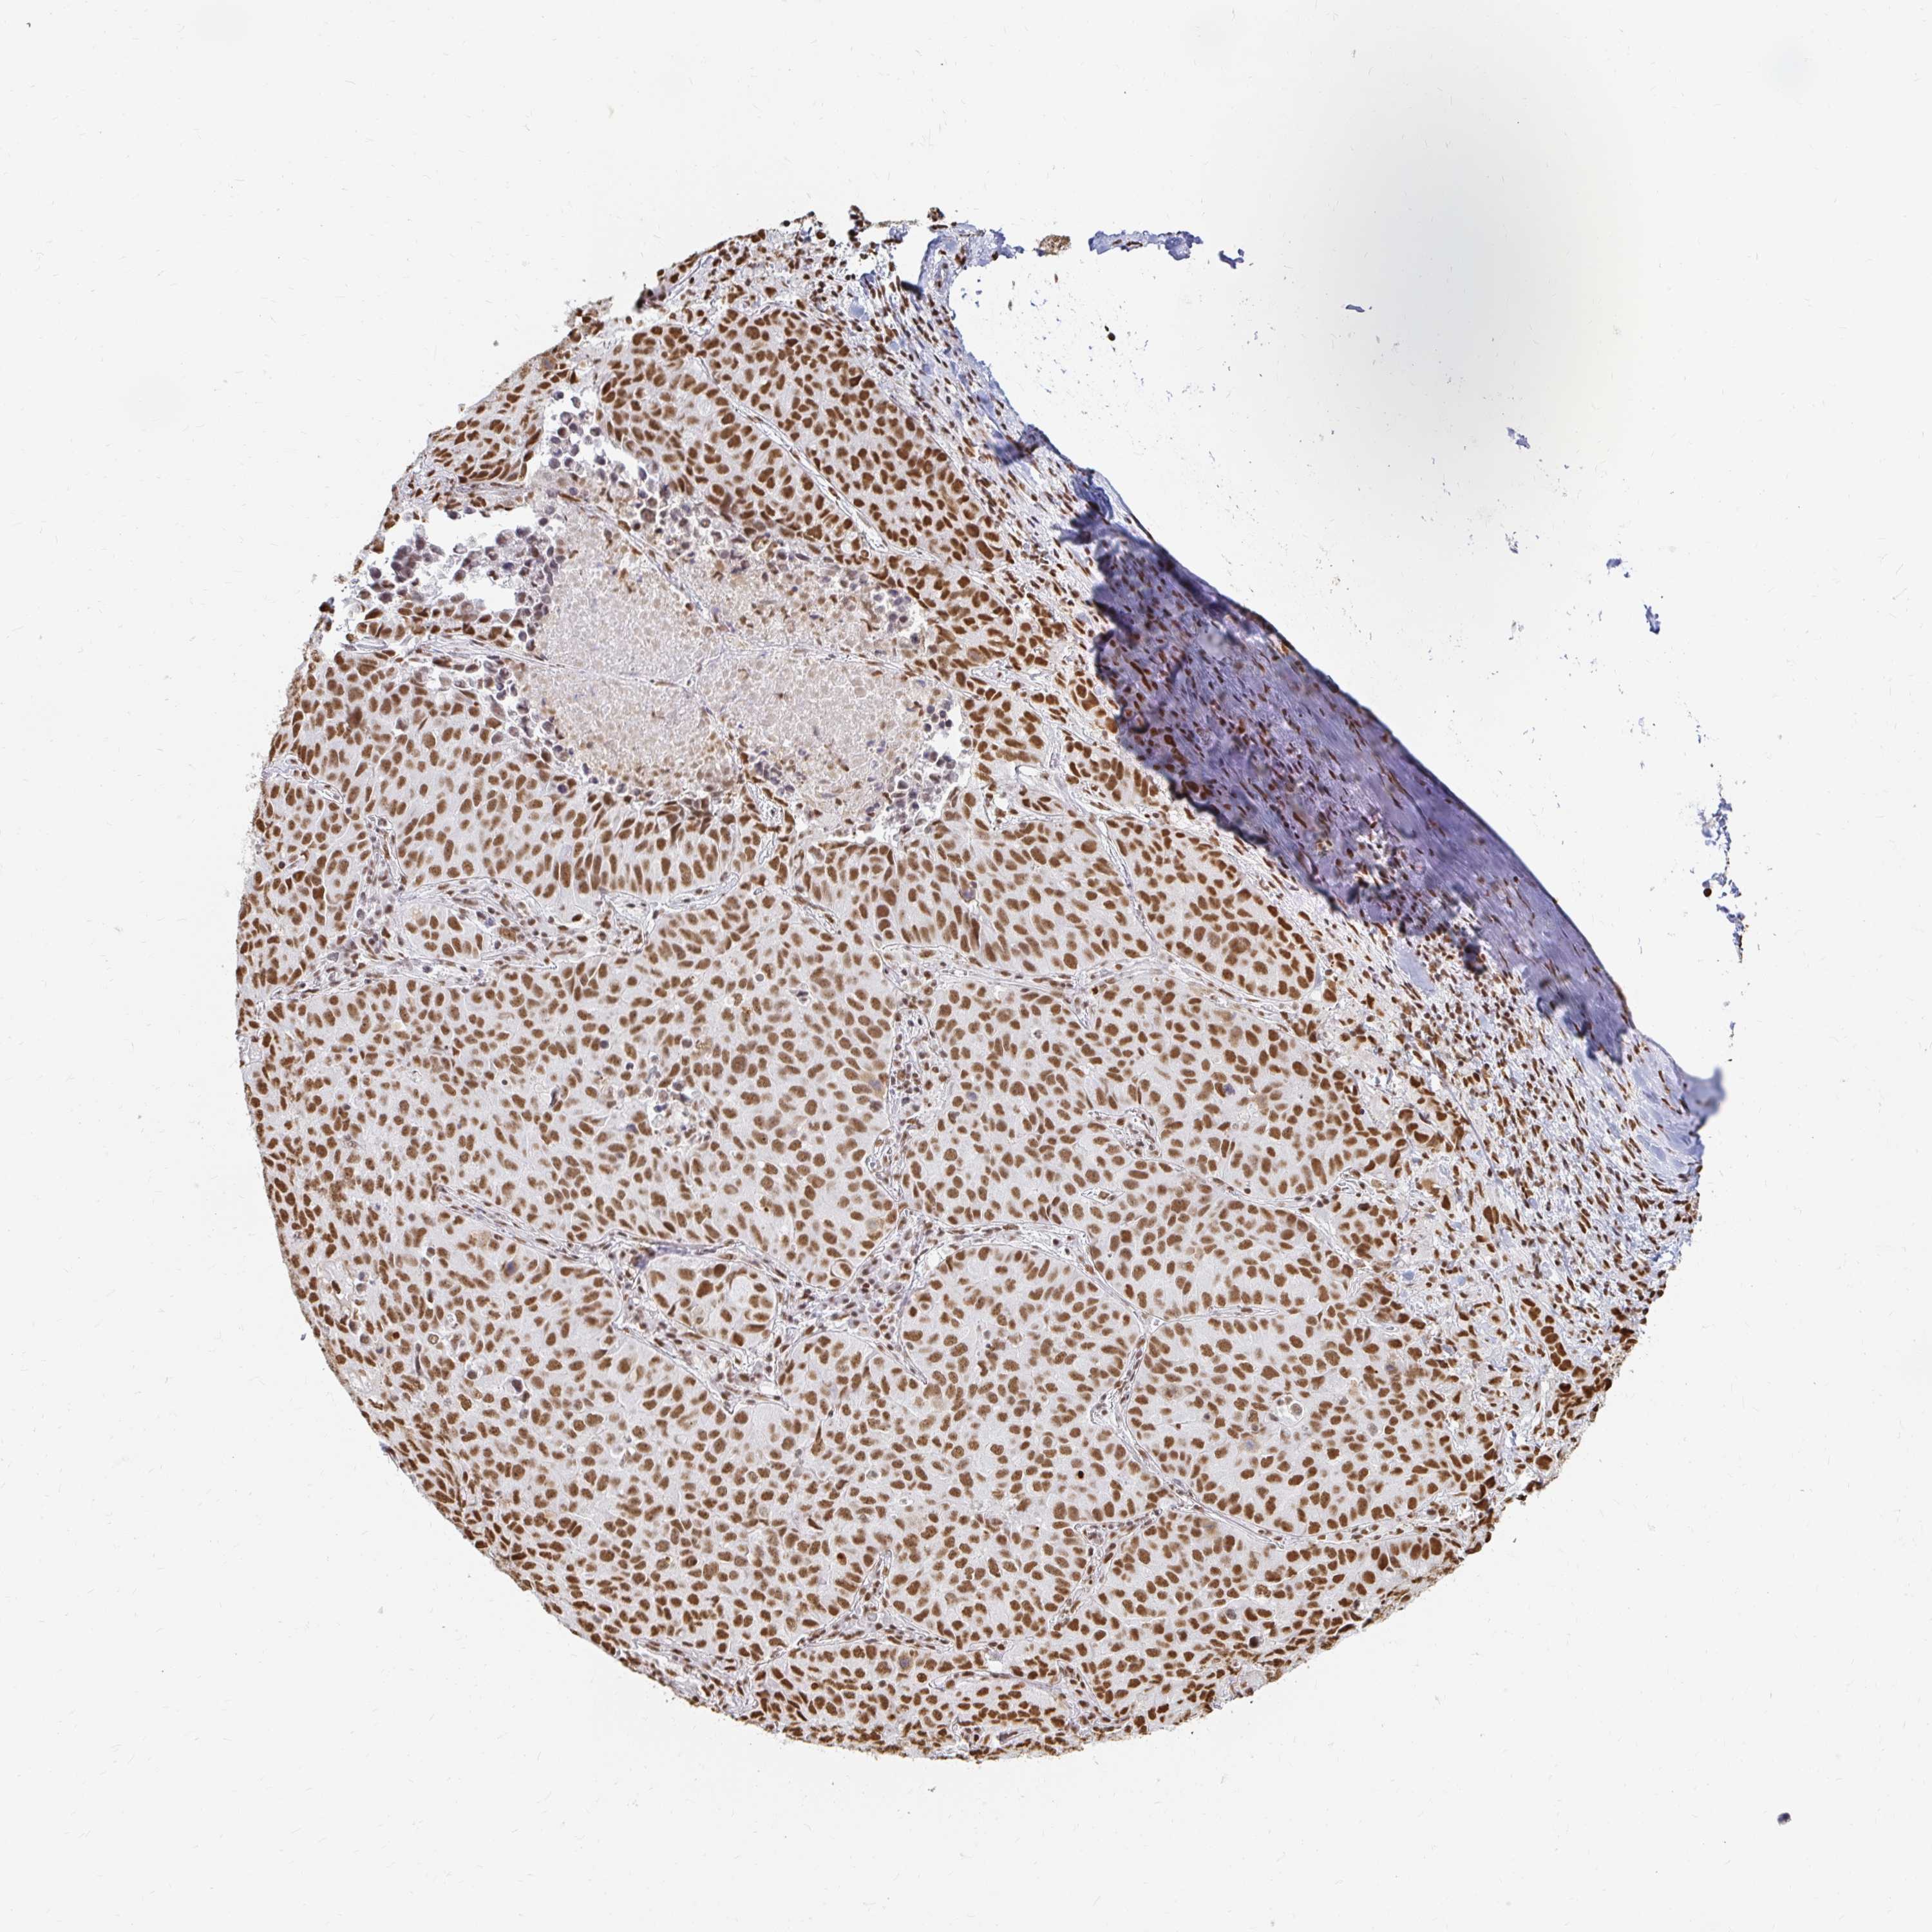

LUNG ADENOCARCINOMA (VALIDATION) - Interactive survival scatter ploti

The Survival Scatter plot shows the clinical status (i.e. dead or alive) for all individuals in the patient cohort, based on the same data that underlies the corresponding Kaplan-Meier plots. Patients that are alive at last time for follow-up are shown in blue and patients who have died during the study are shown in red.

The x-axis shows the expression levels (FPKM) of the investigated gene in the tumor tissue at the time of diagnosis. The y-axis shows the follow-up time after diagnosis (years). Both axes are complimented with kernel density curves demonstrating the data density over the axes. The top density plot shows the expression levels (FPKM) distribution among dead (red) and alive patients (blue). The right density plot shows the data density of the survived years of dead patients with high and low expression levels respectively, stratified using the cutoff indicated by the vertical dashed line through the Survival Scatter plot. This cutoff is automatically defined based on the FPKM cutoff that minimizes the p-score. The cutoff can be changed by dragging the vertical line or by entering a cutoff value in the square labeled "Current cut-off".

Under the Survival Scatter plot the p-score landscape (black curve; left axis) is shown together with dead median separation (red curve; right axis). Dead median separation is the difference in median mRNA expression between patients who have died with high and low expression, respectively. It is calculated as follows: median FPKM expression of dead patients with high expression - median FPKM expression of dead patients with low expression. This is intended to aid the user in visually exploring custom cutoffs and the associated p-scores and dead median separation.

Individual patient data is displayed and can be filtered by clicking on one or more of the category buttons on the top of the page. Categories describing expression level and patient information include: high, low, alive, dead, female, male and tumor stages. The scale of the x-axis can be toggled between linear and log-scale by clicking on the "x log" button. Mouse-over function shows TCGA ID, patient information and mRNA expression (FPKM) for each patient.

& Survival analysisi

Kaplan-Meier plots summarize results from analysis of correlation between mRNA expression level and patient survival. Patients were divided based on level of expression into one of the two groups "low" (under cut off) or "high" (over cut off). X-axis shows time for survival (years) and y-axis shows the probability of survival, where 1.0 corresponds to 100 percent.

HNRNPU is not prognostic in Lung Adenocarcinoma (validation)

Best expression cut offi

Based on the FPKM value of each gene, patients were classified into two groups and association between prognosis (survival) and gene expression (FPKM) was examined. The best expression cut-off refers the FPKM value that yields maximal difference with regard to survival between the two groups at the lowest log-rank P-value. Best expression cut-off was selected based on survival analysis .

When clicking on this number, the vertical dashed line indicating cut-off, the interactive survival plot, and the Kaplan-Meier curve will be adjusted to show results based on the best expression cut-off.

: 116.42

TCGA RNA samplesi

RNA-seq data is reported as average FPKM (number Fragments Per Kilobase of exon per Million reads), generated by the The Cancer Genome Atlas (TCGA) .

Normal distribution across the dataset is visualized with box plots, shown as median and 25th and 75th percentiles. Points are displayed as outliers if they are above or below 1.5 times the interquartile range. FPKM values of the individual samples are presented next to the box plot.

Average pTPM 150.9

Number of samples 105